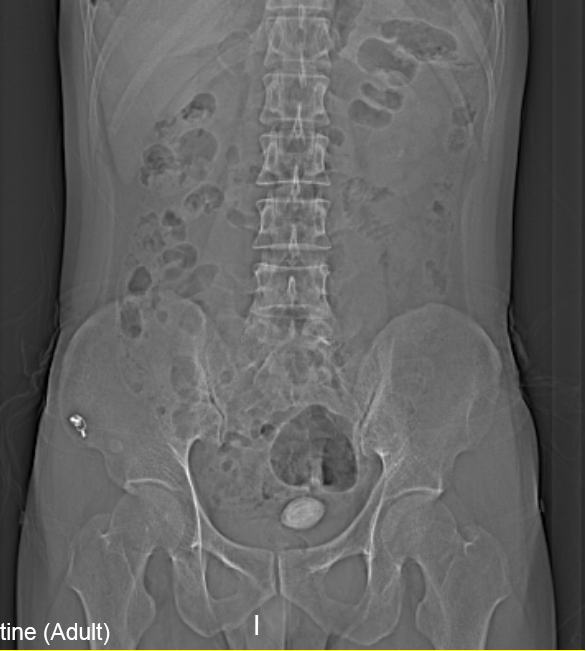

“医生我尿不出,,,,,,尿里有血,,,,,,快帮帮我”。。。。。。。克日,,,,,,在温州市人民医院泌尿外科门诊一位男青年向坐诊的黄来剑主任求助,,,,,,履历富厚的黄主任在相识基本病情后,,,,,,特意触摸了一下患者耻骨上区,,,,,,并嘱咐患者举行泌尿系平片检查,,,,,,效果在意料之中也出乎意料之外。。。。。。。意料之中的是患者诊断如黄主任所想膀胱结石进入尿道卡住了,,,,,,意料之外的是结石直径抵达了35mm,,,,,,像蛋黄巨细了,,,,,,这对年轻患者来说并不常见,,,,,,堵住了尿道,,,,,,把患者痛的够呛。。。。。。。

▲患者影像学检查